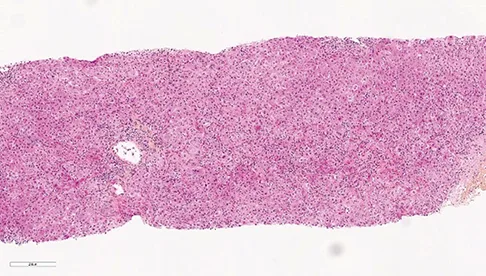

Les patients suivis pour une CBP peuvent présenter des degrés variables d’inflammation hépatique mais habituellement, dans la CBP, on retrouve très peu d’hépatite d’interface ou d’hépatite lobulaire. Environ 8 à 10 % des patients CBP vont présenter des lésions hépatiques faisant évoquer une HAI associée (1, 2). Le syndrome de chevauchement CBP+ HAI peut être présent d’emblée dès le diagnostic initial de la CBP dans 60 % des cas mais les patients CBP peuvent également, dans 30 % des cas, présenter une HAI dite secondaire apparaissant parfois plusieurs années après le diagnostic. Les patients HAI peuvent présenter dans 10 % des cas une CBP dite secondaire (figure 1) (3). Dans le cadre d’une CBP, une augmentation anormalement élevée des transaminases (> 5N) et des IgG (> 20 g/l) doit faire suspecter une HAI associée (4). Des anticorps anti- muscle lisse de spécificité anti-actine et des anticorps anti-ADN double-brin peuvent être présents dans 10 % des cas de CBP. Leur présence doit également faire suspecter l’existence d’un syndrome de chevauchement CBP+ HAI. Dans une étude s’intéressant aux anticorps anti-ADN double brin, ceux-ci étaient présents chez 60 % des patients CBP+ HAI, mais seulement chez 4 % des patients CBP et 26 % des patients HAI (p<0,0001 et 0,01 respectivement). La double positivité d’anticorps anti-ADN double brin et d’anticorps anti-mitochondries était présente chez 47 % des patients CBP+ HAI, mais seulement chez 2 % des pathologies contrôles (5). Dans une autre étude, la présence d’anticorps anti-ADN double brin, une augmentation des ALAT et des IgG étaient les trois facteurs significativement associés aux CBP+ HAI (6). De plus, chez les patients CBP non répondeurs à 12 mois à l’acide ursodésoxycholique (AUDC), une HAI doit être systématiquement recherchée. La présence d’un seul élément évocateur d’HAI n’est en revanche pas suffisant pour poser le diagnostic de syndrome de chevauchement. La réalisation d’une biopsie hépatique, en l’absence de contre-indication, est nécessaire pour confirmer le diagnostic de CBP+ HAI. La présence d’une hépatite d’interface et/ou d’une hépatite lobulaire, bien que non spécifiques, et son intensité permet de confirmer la présence d’une HAI. Le score histologique « modified HAI » (mHAI) développé par Ishak et al. permet de décrire l’activité hépatique inflammatoire et définit les indications de traitement (7, 8). Ce score décrit 4 catégories d’inflammation nécrotico-inflammatoire : l’hépatite d’interface périportale, la nécrose confluente, l’inflammation lobulaire et l’inflammation portale (figure 2). Un score mHAI> 4 est une indication de traitement immunosuppresseur. Les critères de Paris définis par Chazouillières et al. sont cependant les plus couramment utilisés et recommandés par la société européenne pour l’étude du foie (EASL) pour poser le diagnostic de syndrome de chevauchement CBP+ HAI. Ils reposent sur la présence d’au moins deux critères sur trois de CBP : PAL> 2N ou GGT> 5N ; anticorps anti mitochondries≥ 1/40 ; lésions biliaires florides à l’histologie et d’au moins deux critères sur trois d’HAI : ALAT> 5N ; IgG sériques> 2N ou présence d’anticorps anti muscle lisse ; une hépatite d’interface modérée à sévère en histologie (tableau 2, figure 2) (1). Dans une étude publiée en 2010, la sensibilité et la spécificité des critères de Paris pour diagnostiquer une CBP+ HAI étaient respectivement de 92 % et 97 % (9). Le score de Paris est un score différent de ceux utilisés pour faire le diagnostic de chaque pathologie propre CBP ou HAI. Le groupe de travail international de l’HAI ne recommande pas l’utilisation des scores diagnostiques habituels d’HAI (corrigés ou simplifiés) pour faire le diagnostic de CBP+ HAI du fait de leurs très faibles sensibilité et spécificité (9-12). L’objectif de poser un diagnostic de syndrome de chevauchement, et de manière précoce, est de pouvoir proposer un traitement adapté, notamment immunosuppresseur afin d’éviter la progression de la fibrose. Néanmoins, il est important de ne pas porter de diagnostic par excès afin d’éviter aux patients des effets secondaires d’une corticothérapie et/ou d’un traitement immunosuppresseur qui peuvent être sévères.

Figure 2 : Lésions histologiques biliaires évocatrices de CBP (A, B, C), lésions histologiques d’hépatite d’interface et d’hépatite lobulaire évocatrices d’HAI (D, E, F).